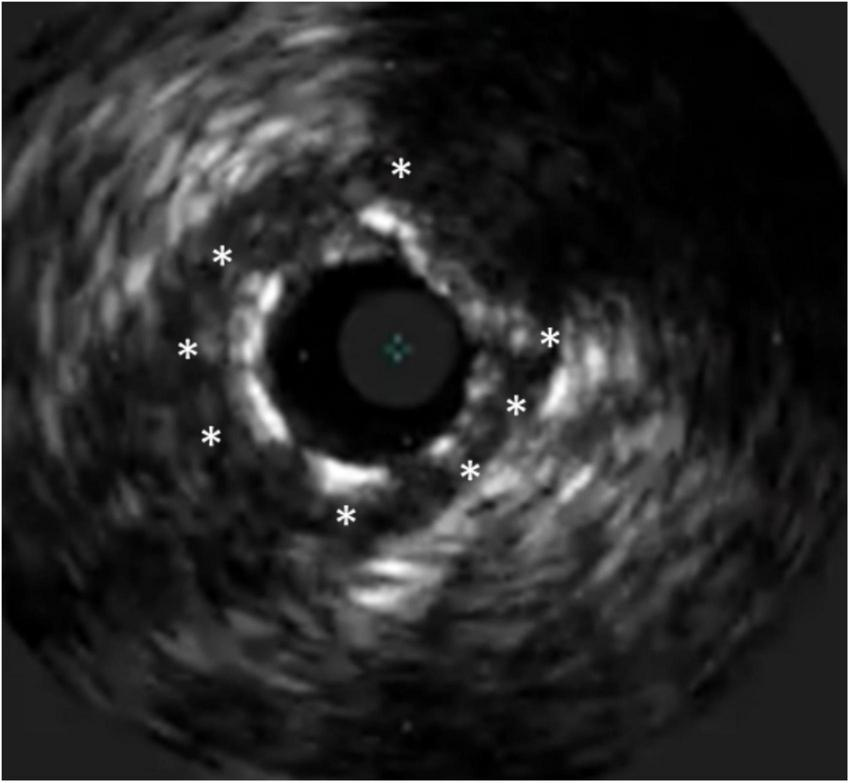

FIGURE 5

Stent undersizing demonstrated at IVUS. The white dotted line marks the lamina externa, where the stent struts (*) should lie.

Imaging-guided stent sizing is based on either the external elastic lamina (EEL) diameters of the distal reference, usually rounded down by ≥0.5 mm or alternatively, reference lumen diameters can be used, rounded up by 0.5 mm. Particularly in smaller or very calcific arteries, or in the setting of diffusely diseased vessels (including chronic total occlusions) or acute coronary syndromes, imaging-guided sizing is often larger than the angiographic reference diameters.

For its superior capacity to distinguish the EEL, IVUS is considered to be the gold standard method for guiding stent sizing (Figure 5). Because of the limited tissue penetration of OCT (1–2 mm) compared to IVUS (5–6 mm), it is often not able to visualize the EEL at the lesion site. The introduction of artificial intelligence-based methods in the latest iteration of the OCT software by the company Abbott vascular, however, significantly streamlines these processes (Figure 6). Therefore, an algorithm was proposed by the ILUMIEN III and IV studies (54, 69), where the EEL diameter was used if the EEL circumference was visible for ≥180°. In such case, the proximal and distal reference mean EEL diameters were measured, and the smaller of these diameters rounded down to the nearest 0.25 mm was used. In case the EEL cannot be seen ≥180°, the stent diameter was determined as 100% of the lumen diameter. Compared to the respective reference, a final lumen area ≥90% was considered acceptable. Using this algorithm, OCT-guided PCI was non-inferior to operator-directed IVUS guidance in terms of the post-PCI MSA, with no difference in procedural MACE up to 1 year (54, 68). Because ILUMIEN III was underpowered to detect differences in clinical outcomes, another adequately powered ongoing trial, ILUMIEN IV trial (NCT03507777), is geared to rigorously test this aspect (69).